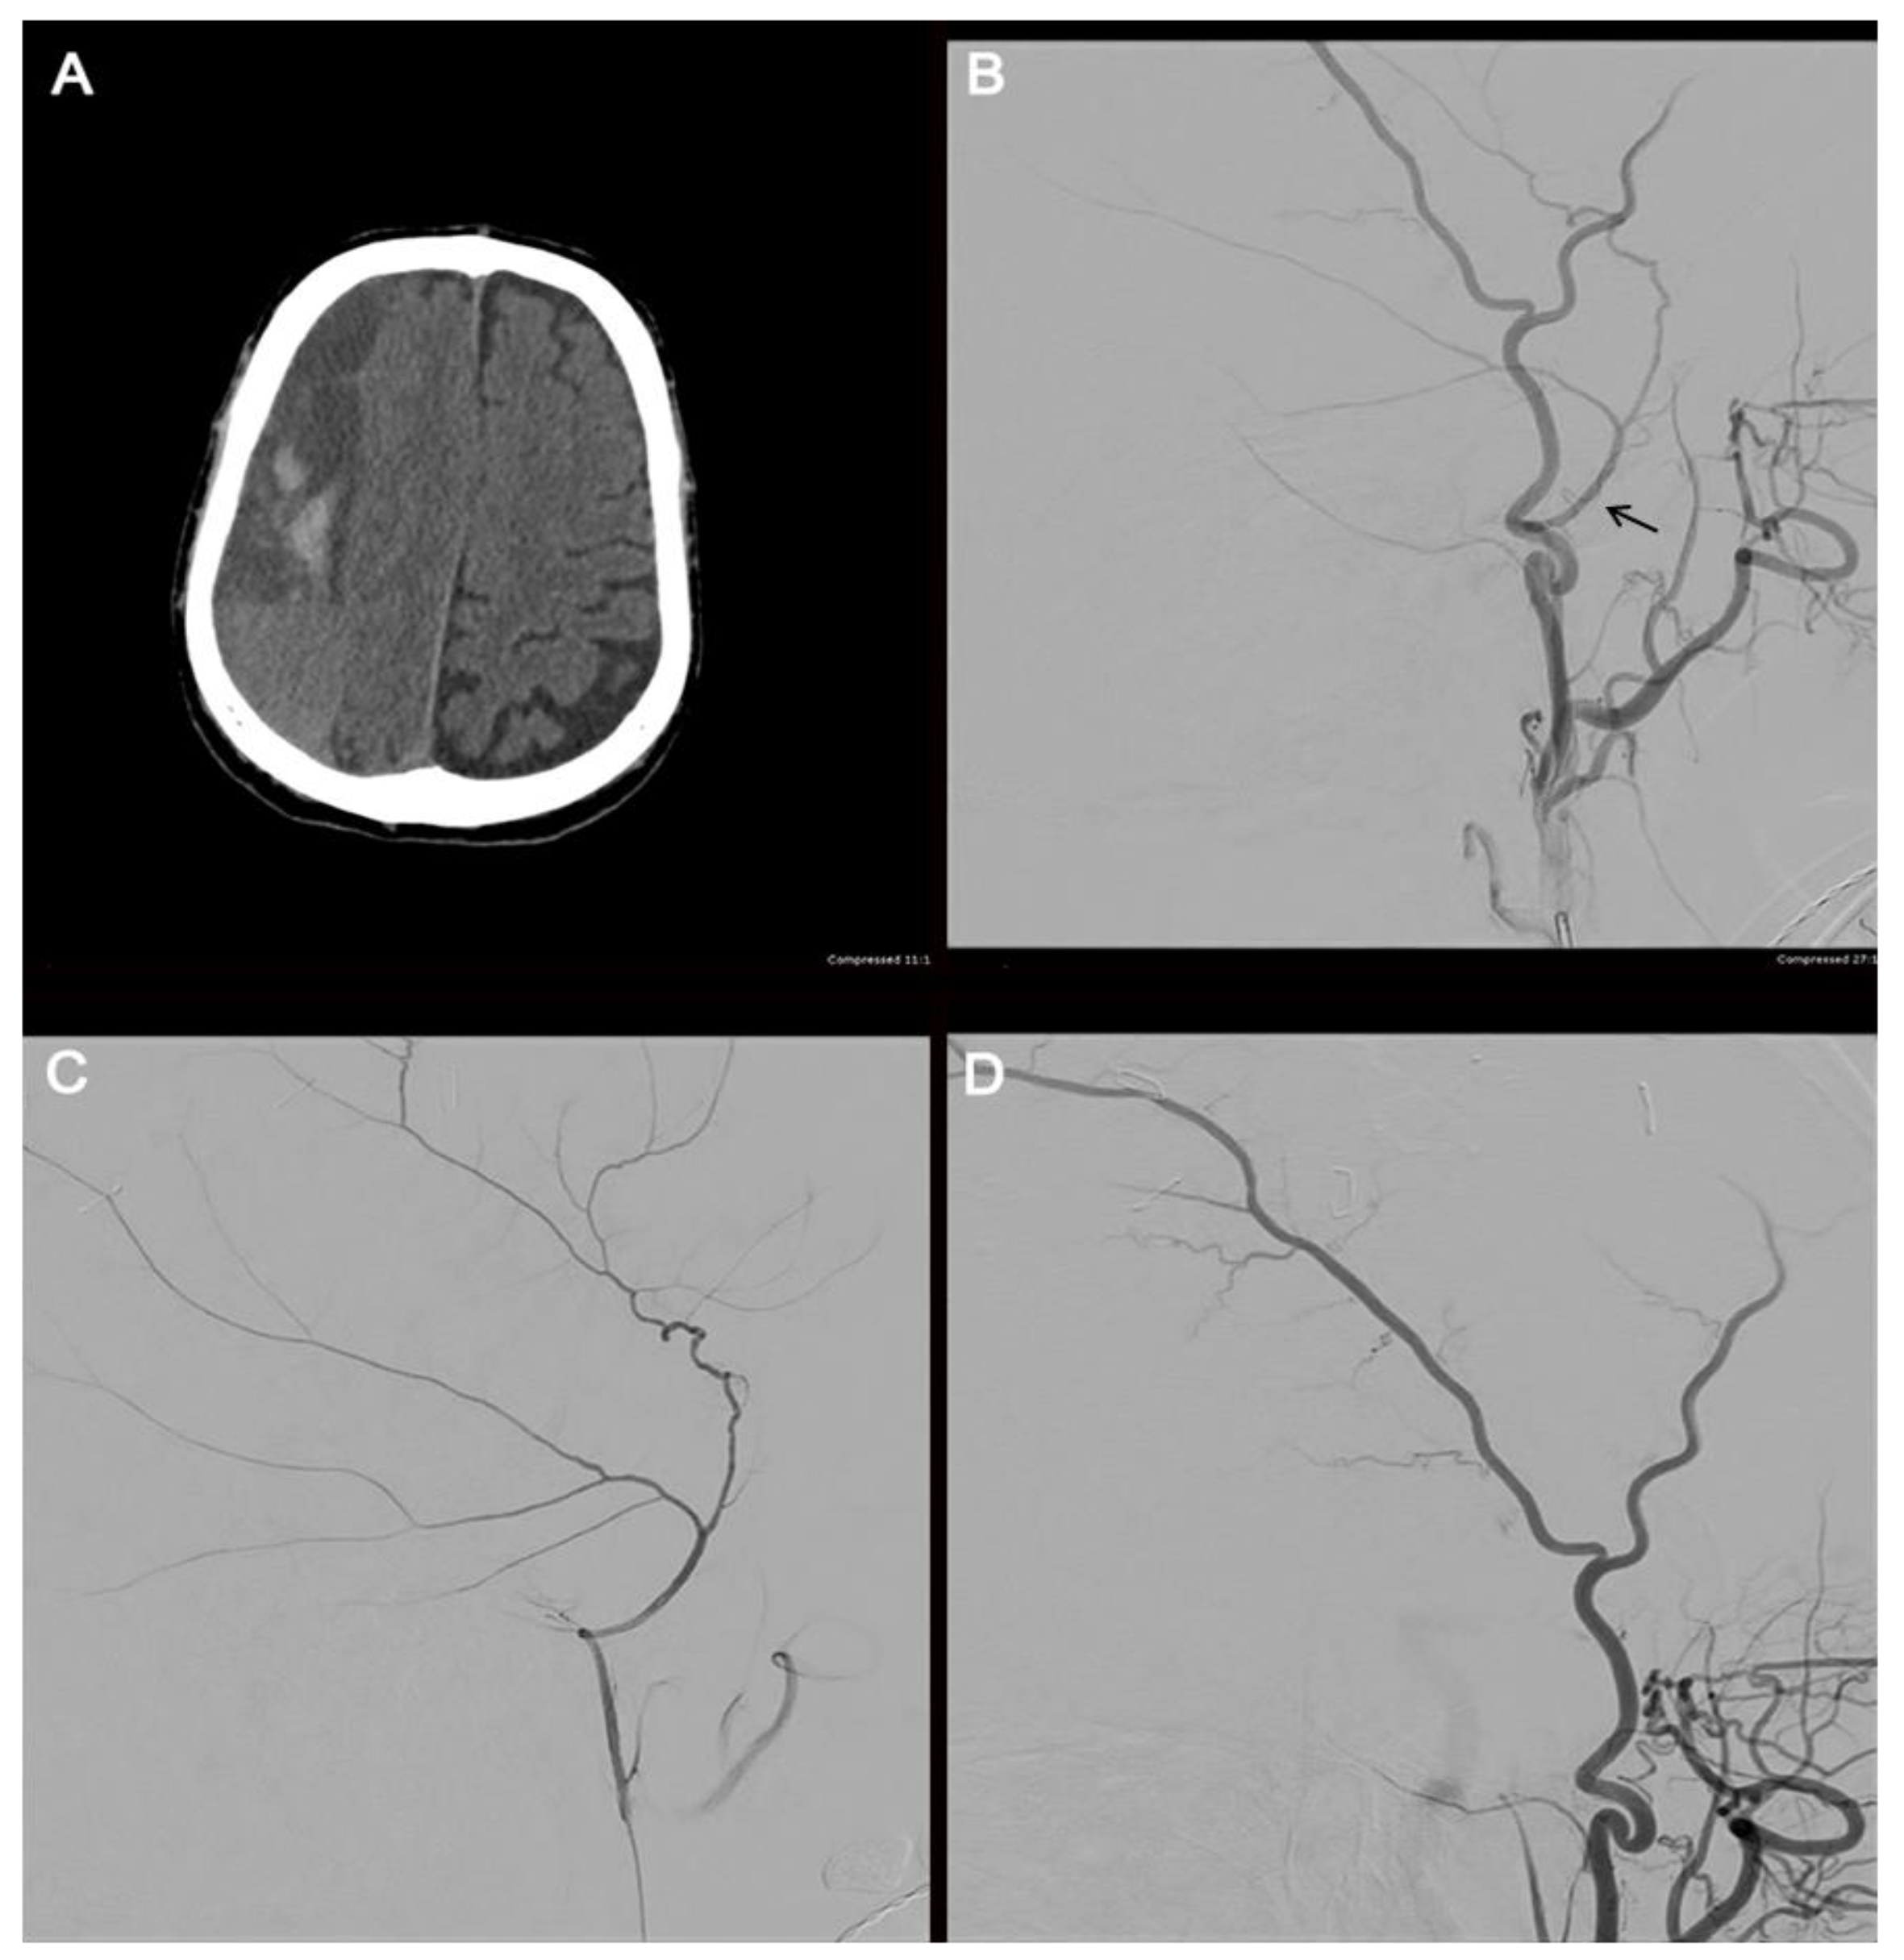

Embolization may be performed with microparticles, onyx, n-butyl cyanoacrylate, or coils. A recent systematic review found that polyvinyl alcohol (PVA) was the most used embolic agent; however, the efficacy and rate of complications were not affected by the choice of embolisate [114]. Before embolization, selective angiography of the MMA is performed to target the branches of interest and avoid potentially dangerous collaterals (Figure 4). When flow stasis is observed in the MMA, the procedure is concluded.

Illustrative case. The radiographic course of an 82-year-old male who presented with a large, septated, chronic right-sided SDH (A). The patient underwent a cerebral angiogram with embolization of the right middle meningeal artery using 50–150 µm Embospheres. An external carotid artery angiogram (B) shows the filling of the middle meningeal artery (arrow). A selective middle meningeal artery angiogram was then performed (C). A post-embolization angiogram of the external carotid artery shows no filling of the middle meningeal artery (D).